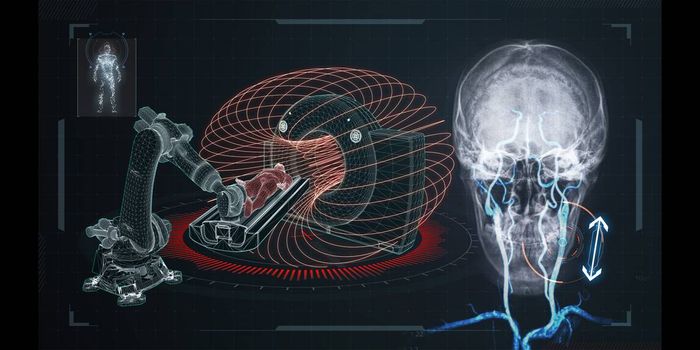

JUN 07, 2020Chemistry & PhysicsScientists from the University of Nottingham have published their most recent developments on a wearable 49 channel brai ...